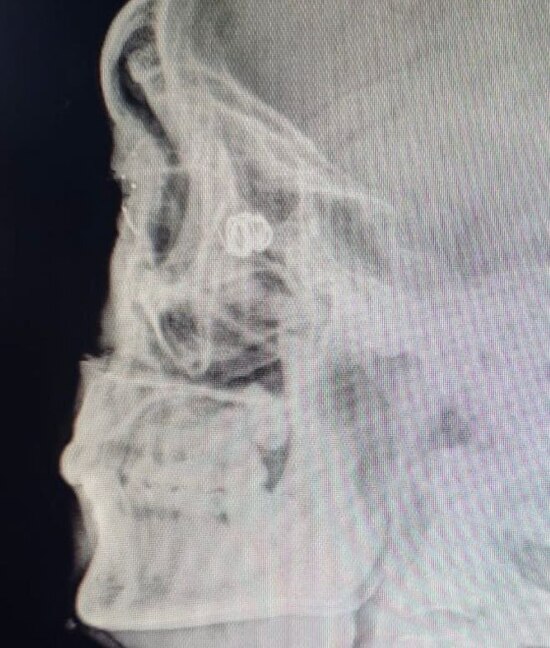

В своём докладе она представила опыт республики в лечении пациентов, получивших боевые ранения, включая повреждения глазного яблока и придаточного аппарата глаза после воздействия взрывной волны и осколков. Особый интерес вызвала разработанная ею собственная методика удаления инородных тел, расположенных в орбите за глазом.

Методика может применяться даже в условиях госпиталей, где нет компьютерного томографа. Она позволяет безопасно извлекать инородные тела из труднодоступных областей орбиты, снижая риск повреждения зрительного нерва и других важных структур. Николаева подробно показала этапы вмешательства — от диагностики до результатов восстановления.